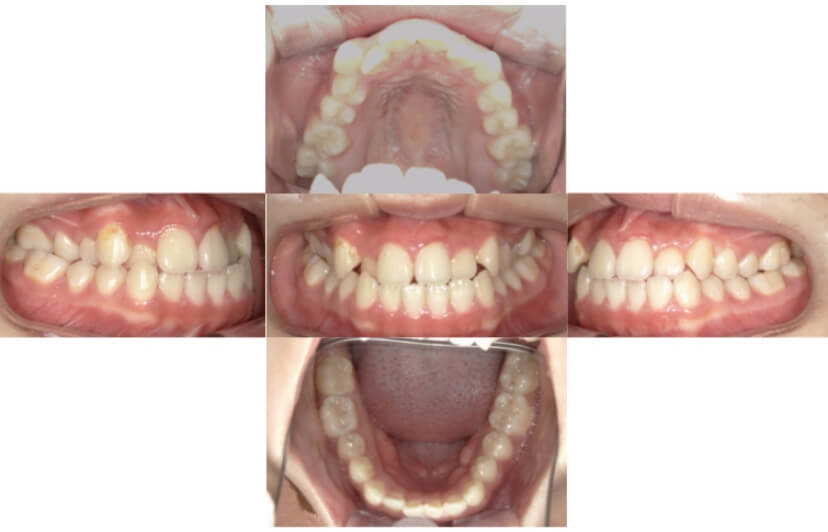

BEFORE

AFTER

症例2

上下顎前突、叢生

抜歯

ブラケット矯正

上下顎前突、叢生(上下出っ歯、上下の前歯のガタガタ)のケースです。

装置はラビアル(上下表側)で、上下顎の小臼歯を4本抜歯を行っています。抜歯したスペースを使って、上下の前歯の後方移動と叢生(ガタガタ)の改善を行っています。

主訴 前歯のガタガタと口元がでているのが気になる。

年齢・性別 30歳 女性

お住まいの地域 東京都大田区

治療方針 抜歯スペースを利用して上前歯の叢生(ガタガタ)と口元突出の改善

抜歯部位 上下顎左右第一小臼歯

使用装置 ラビアル(上下表側)、顎間ゴム

治療期間 1年11か月

治療回数 13回

リテーナー クリアリテーナー